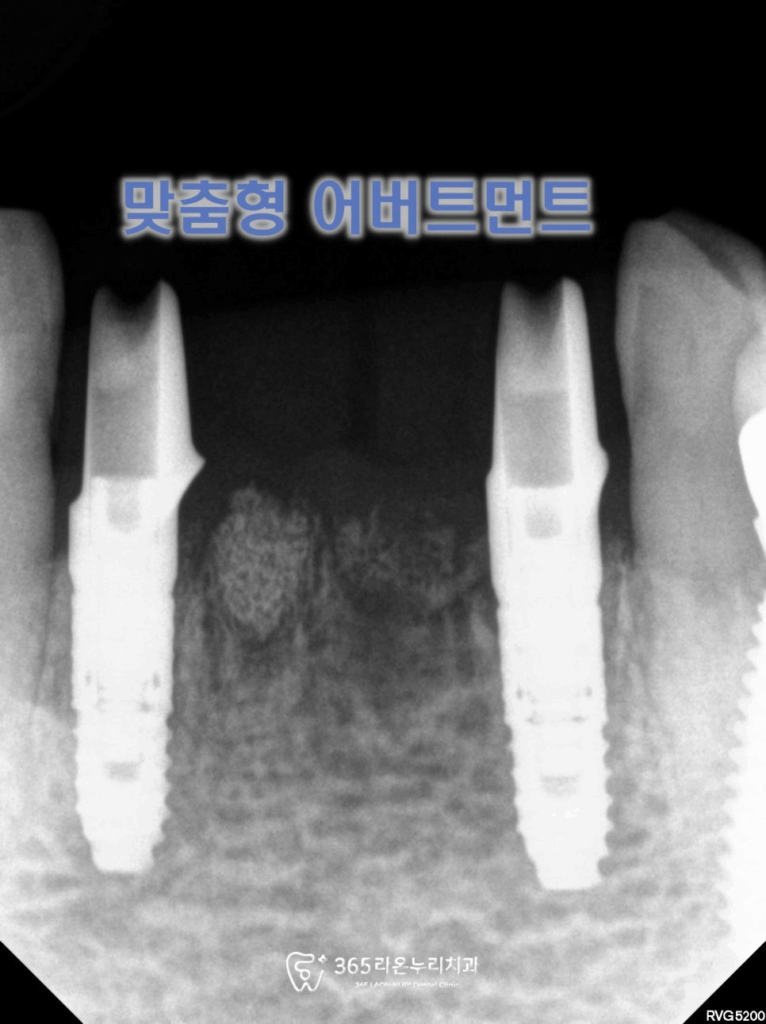

뼈와 잘 붙은 것을

확인했을 때,

2025.5.30

맞춤형 어버트먼트를

제작하게 됩니다.